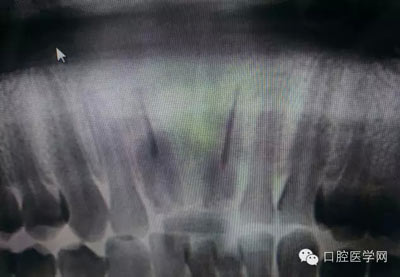

深齲或者是齲壞備洞的時候意外穿髓,我們怎么處理好些?后期出現(xiàn)的牙髓的癥狀,是我們操作的問題?比如細菌層的存在,我們沒有清理干凈?還是我們窩洞沒有進行消毒,或者是隔濕沒有做好導致的粘結(jié)出現(xiàn)問題,還是材料充填的時手法不對,導致的材料收縮過大,還是我們的光照設(shè)備出現(xiàn)了老化沒有完全達到想要的固化,還是懸空的釉質(zhì)沒有去除導致的微滲漏的發(fā)生,或者是材料本身對牙髓產(chǎn)生的刺激,還是材料選擇的問題,或者是我們對材料的性能和說明沒有足夠的了解導致的,沒有按照材料的要求去做,還是我們自身對牙齒情況的判斷出現(xiàn)的問題......

這是一例外院樹脂修復后十個月出現(xiàn)牙髓炎癥狀的患者。遇到這樣子的患者大家會怎么做,證明選擇,還有就是可做可不做治療的如何去平衡。